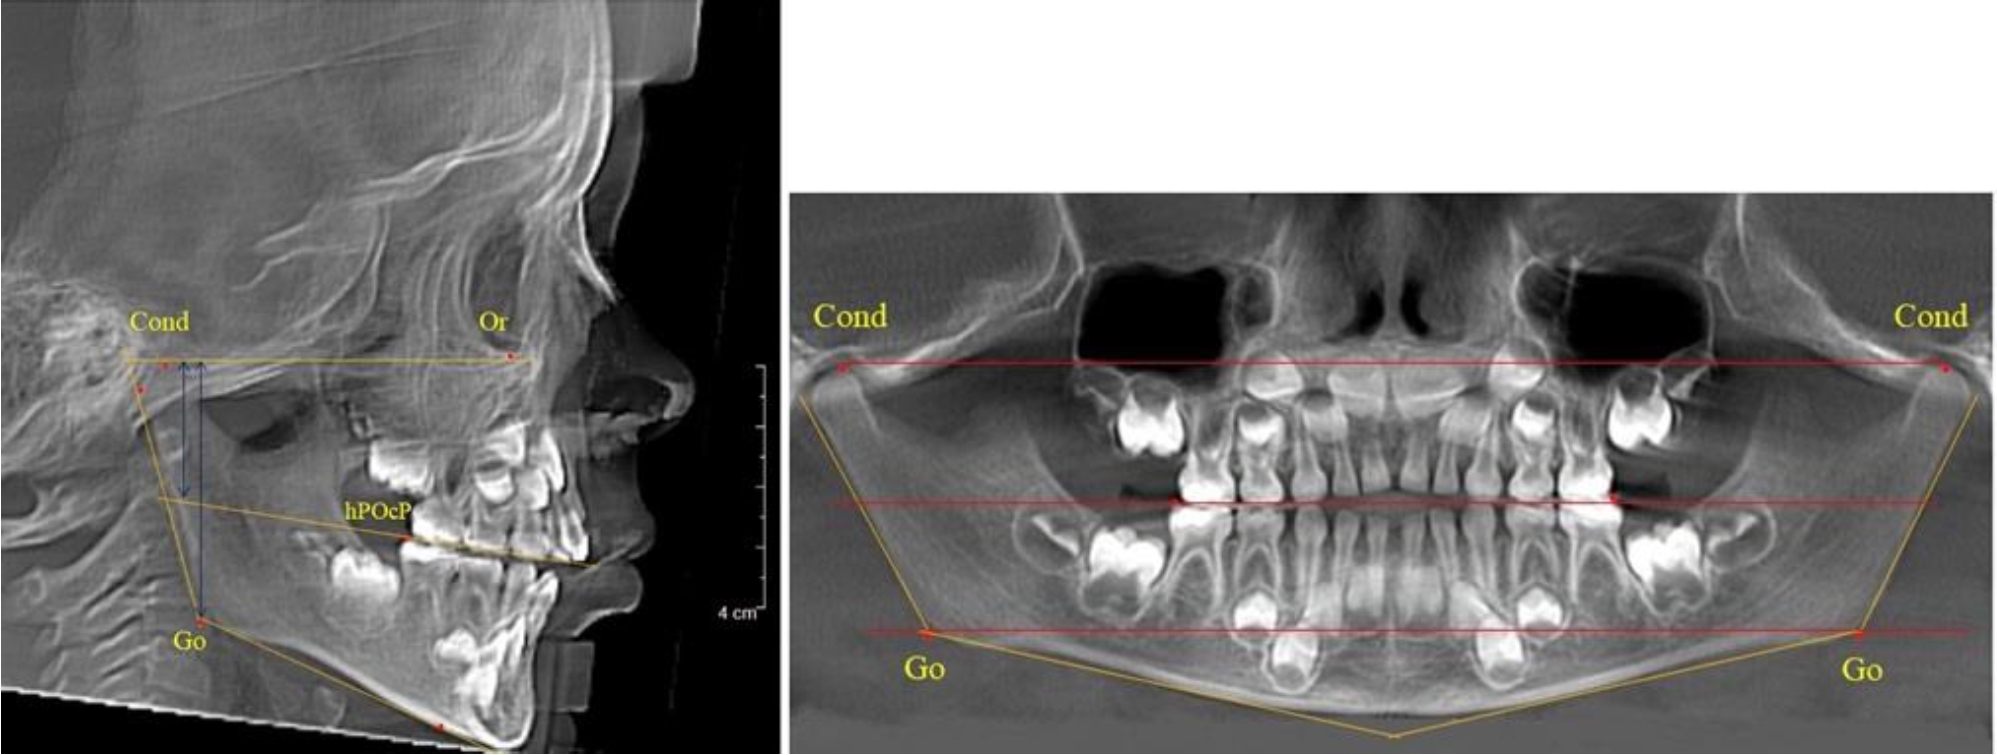

На боковых телерентгенгенограммах вершину суставной головки обозначали точкой кондиион Cond. Касательные линии к ветви и телу нижней челюсти пересекались в точке, которую обозначили Go. Точкой hPOcP обозначали дистальный бугорок нижнего второго моляра вблизи окклюзионного контура коронки. Указанный ориентир соединяли с межрезцовой точкой при построении окклюзионной линии. Высота ветви определялась расстоянием Go-Cond. Окклюзионная линия служила границей между верхней (окклюзионно-суставной) линией и нижней (окклюзионно-альвеолярной) линией.

На ортопантомограмме точки Cond соединяли между собой суставной линией Cond-Cond. Касательная к ветви нижней челюсти соединяла выступающие точки, которые соединялись в области угла и определяли положение точки гонион Go с обеих сторон, которые соединяли гониональной линией Go-Go.

Горизонтальная линя, соединяющая окклюзионные точки hPOcP, определялась как окклюзионная горизонталь.

Расстояние между горизонталями в области ветвей челюсти измеряли электронным штангенциркулем с точностью до сотых долей миллиметра.

Во 2-й группе были проанализированы 11 телерентгенограмм и 11 ортопантомограмм, что составило (10,38 ± 2,96) % от числа изученных рентгенограмм. На всех рентгенограммах первые постоянные моляры были установлены в окклюзии, и произошла смена нижних медиальных резцов.

На всех парах рентгенограмм угол нижней челюсти, измеренный на телерентгенограмме, так же, как и в 1-й группе, соответствовал углу, полученному при построении угла на ортопантомограмме. Окклюзионная линия делила ветвь на два отдела (рис. 2).

Рис. 2. ТРГ и ОПТГ пациента после прорезывания первых постоянных моляров

Как на ортопантомограмме, так и на телерентгенограмме высота ветви у детей 2-й группы составляла (46,54 ± 2,87) мм, что было несколько больше, чем у детей 1-й группы (р ˂ 0,05). При этом высота верхней окклюзионно-суставной части была (25,42 ± 1,59) мм, а нижней – (21,12 ± 1,77) мм.

Таким образом, верхняя часть была несколько больше нижней, что и определяло рост обеих частей ветви.

Относительные показатели соразмерности частей ветви нижней челюсти показали, что отношение высоты верхней части ветви к нижней в среднем составляло 1,21 ± 0,12. Отношение общей высоты ветви к верхней ее части составляло 1,83 ± 0,13, а отношение общей высоты ветви к нижней ее части было 2,20 ± 0,16, и достоверных различий по относительному показателю отношения всей высоты к верхней и нижней челюсти нами не отмечено (р ˃ 0,05).